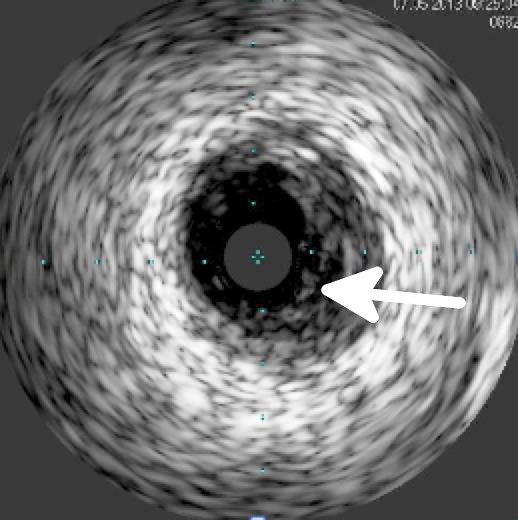

Intravaskulärer Ultraschall (IVUS)

Der intravaskuläre Ultraschall (IVUS) ist eine invasive, bildgebende Untersuchungsmethode. Durch den Einsatz des IVUS wird die intravasale Bildgebung möglich. Verengungen von Koronararterien (Koronarstenosen), die angiographisch schwer zu interpretieren sind, können durch den IVUS präziser dargestellt werden.

Gefäß vor Implantation

Besonders die Einschätzung der Stenoselänge und der Wanddimensionen erlaubt dem Untersucher eine möglichst optimale Ballon- bzw. Stentauswahl, was in mehreren Studien zu einer deutlichen Verbesserung der Langzeitergebnissen führte.

An der Spitze des IVUS-Katheters ist eine „kleine“ Ultraschalleinheit angebracht, die Schallwellen im Hochfrequenzbereich (20-50 MHz.) aussendet und hierdurch ein Abbild der Gefäßwand erzeugt.